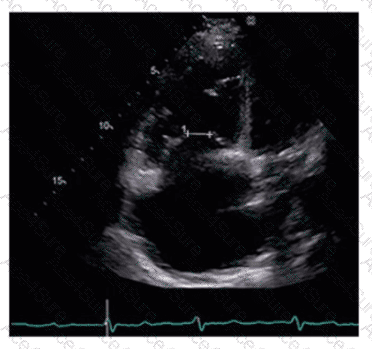

What can be concluded about the tricuspid valve demonstrated in this image?

The image shows incomplete leaflet apposition of the tricuspid valve leaflets with a visible gap, indicating malcoaptation. This is a common cause of tricuspid regurgitation due to leaflet tethering or annular dilation.

Normal coaptation would show complete leaflet closure. Stenosis would show restricted leaflet motion but not malcoaptation. Endocarditis involves vegetations and leaflet destruction, which are not evident here.